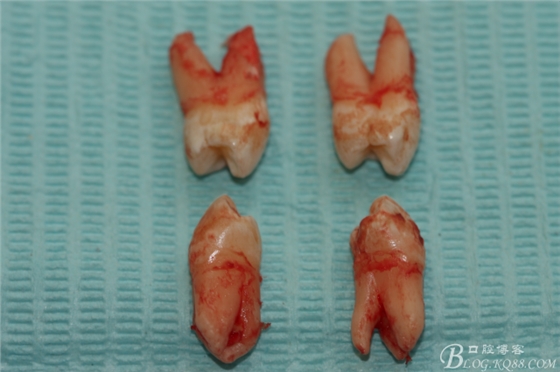

患者:江某某、男、14歲。因正畸治療需要拔除上下頜四顆第一前磨牙。按醫(yī)囑,局麻下拔除四顆第一前磨牙。牙齒拔除后發(fā)現(xiàn)四顆牙齒均為三個(gè)根,頰側(cè)兩根,腭側(cè)一個(gè)根。上頜第一前磨牙偶見(jiàn)三根。下頜第一前磨牙左右兩側(cè)均為三根,實(shí)屬罕見(jiàn)。發(fā)圖片,與同仁共勉。

7.四顆離體上下頜第一前磨牙牙根形態(tài)